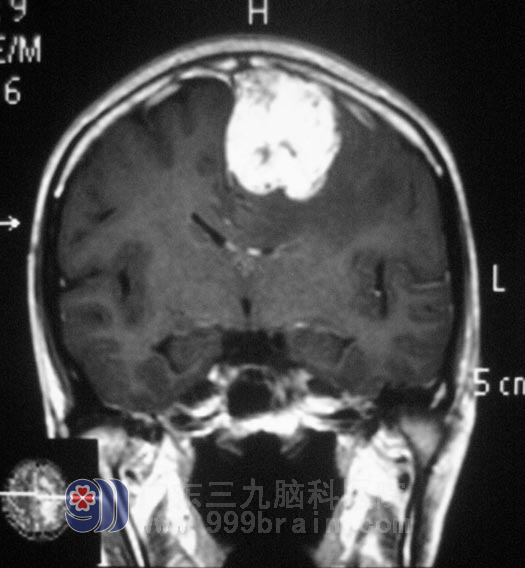

经过一段时间的休养,阿花在家人的陪同下住进了广东三九脑科医院综合神经外科,鲁明主任亲自为她行左侧额顶大脑镰旁占位病变切除术,肿瘤位于矢状窦左侧,表面回流静脉充盈,并向矢状窦汇集,沿肿瘤边界向大脑镰仔细分离并切除肿瘤,肿瘤血供稍丰富,向额叶方向分离后见肿瘤供血动脉,沿肿瘤边界分离,全切肿瘤,将大脑镰壁上残留肿瘤组织清扫。手术后她的病情稳定,恢复得很好,病理结果是:(左侧额顶部)脑膜瘤,WHOI 级。http://www.999brain.com/

▲手术前